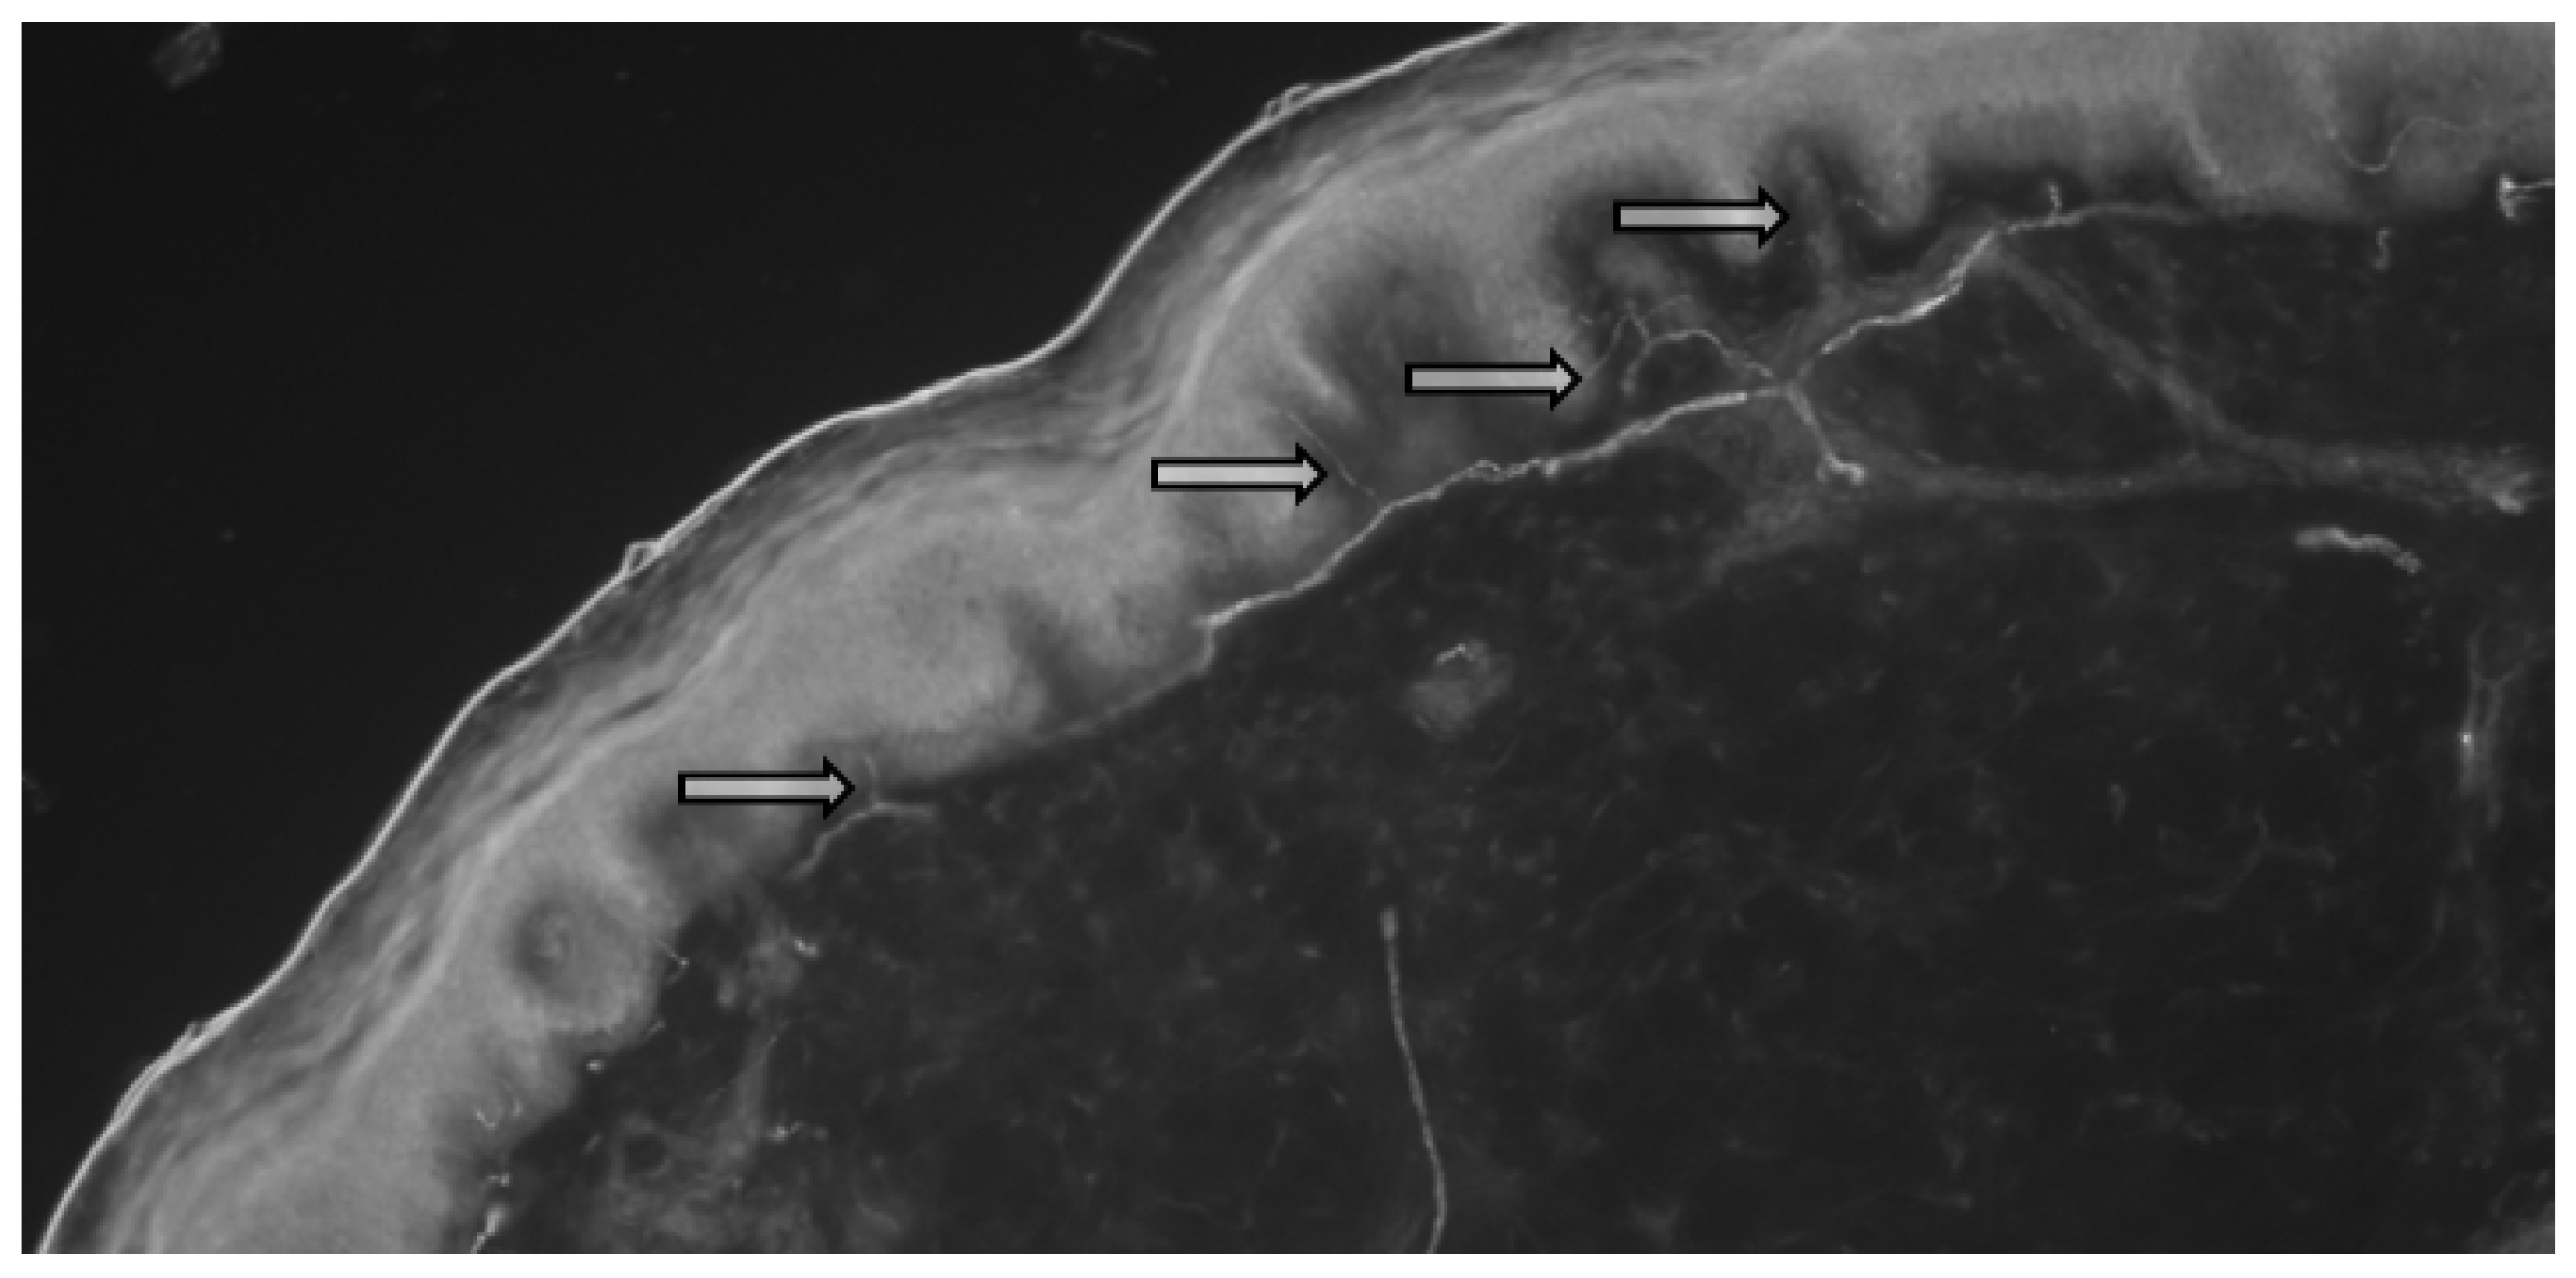

A total of 13 biopsy specimens were obtained from the patients with sarcoidosis, where the intraepidermal density (IEFD) of the small nerve fibers was calculated (Figure 1 and Figure 2).

Figure 1. Skin biopsy of patient with sarcoidosis (enzyme immunoassay, male, 34 years). Arrows indicate small fibers in the epidermis of the skin.